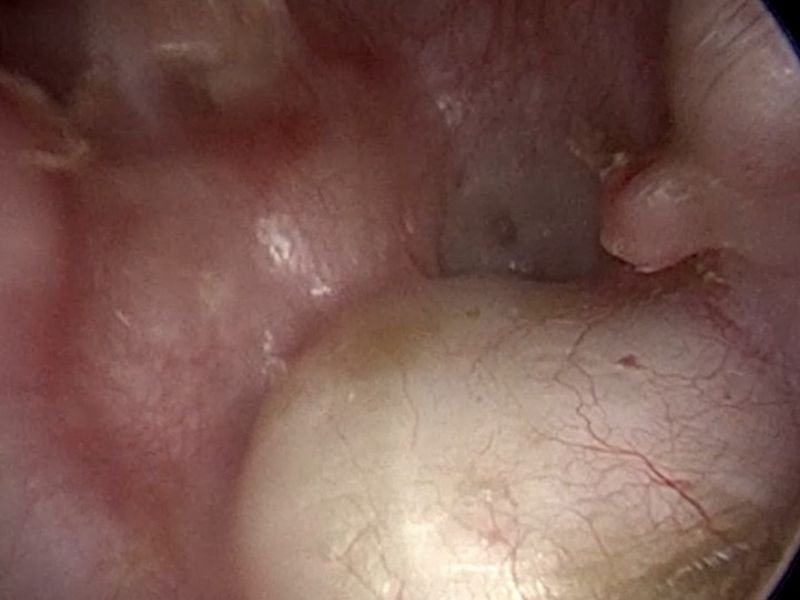

A otorrinolaringologia combina conhecimento clínico com tecnologias avançadas para diagnosticar a surdez. Entre os principais métodos usados em Florianópolis estão:

• Impedanciometria: Mede a resposta do tímpano e a integridade do sistema auditivo médio.

Além desses exames, os especialistas em Florianópolis analisam o histórico clínico e os sintomas do paciente, como zumbido, dor no ouvido ou dificuldade para compreender palavras. O uso combinado dessas abordagens permite um diagnóstico preciso e personalizado.